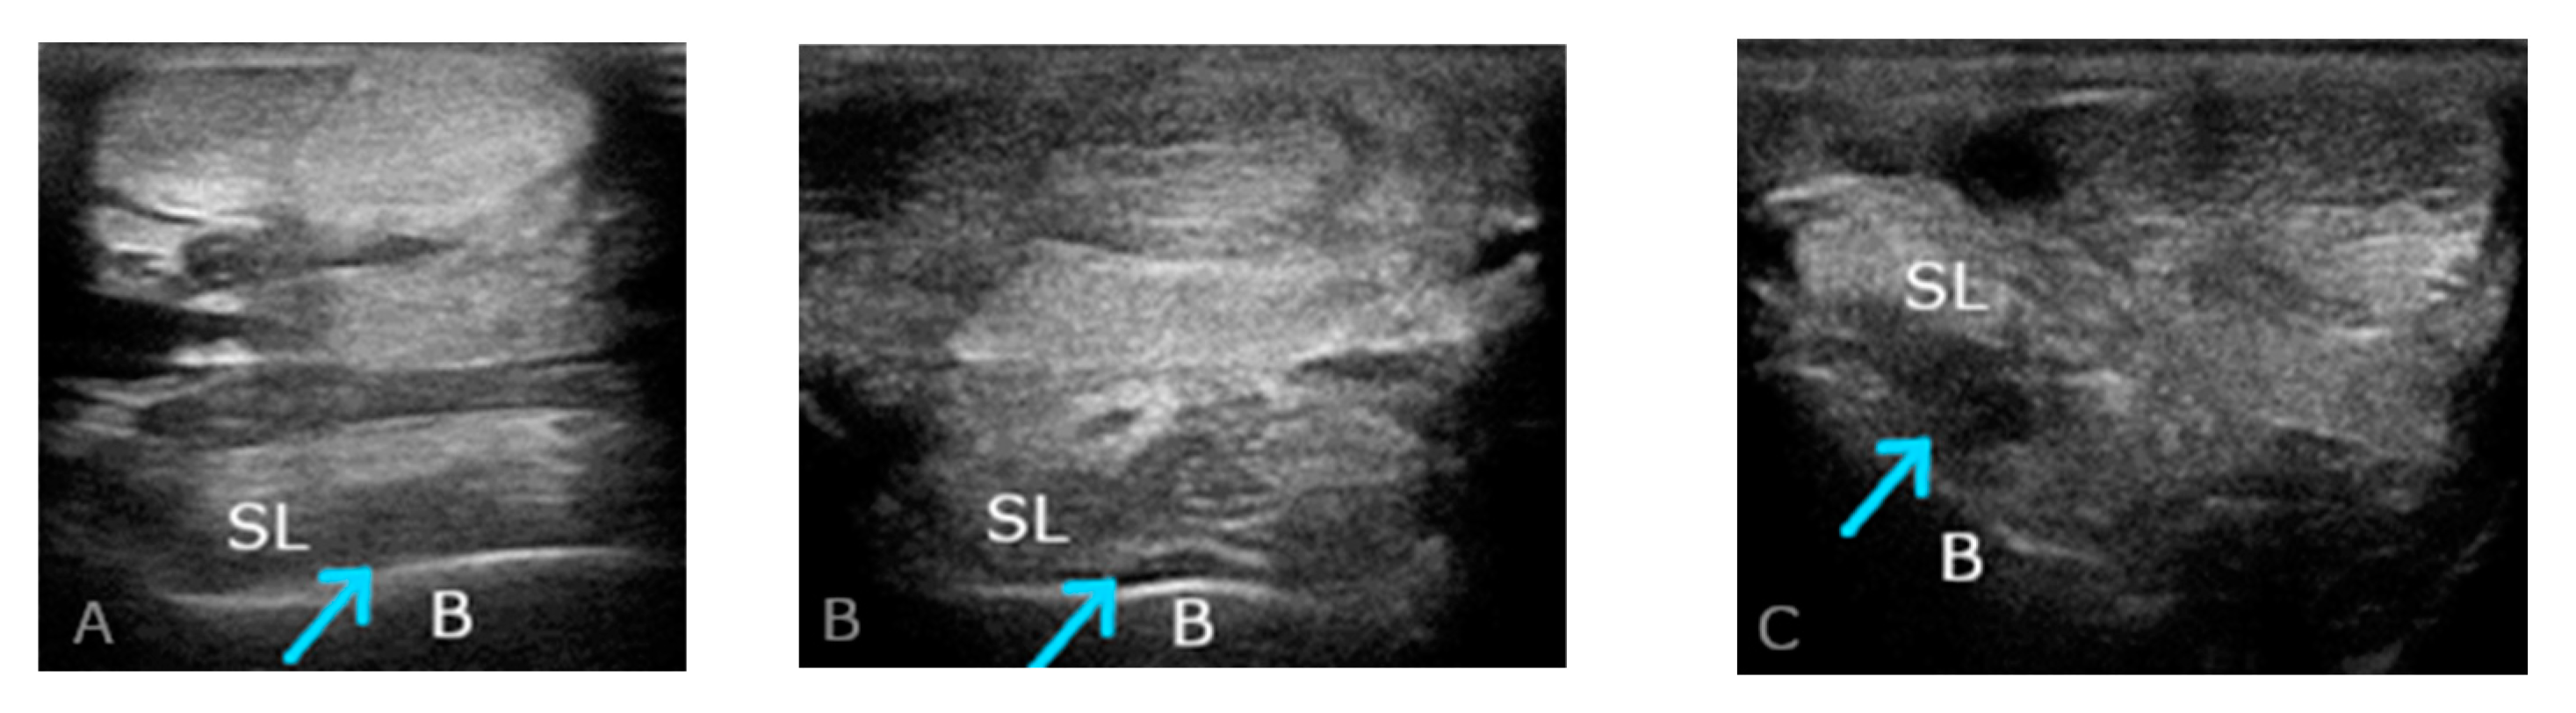

2.2. Ultrasound Examination